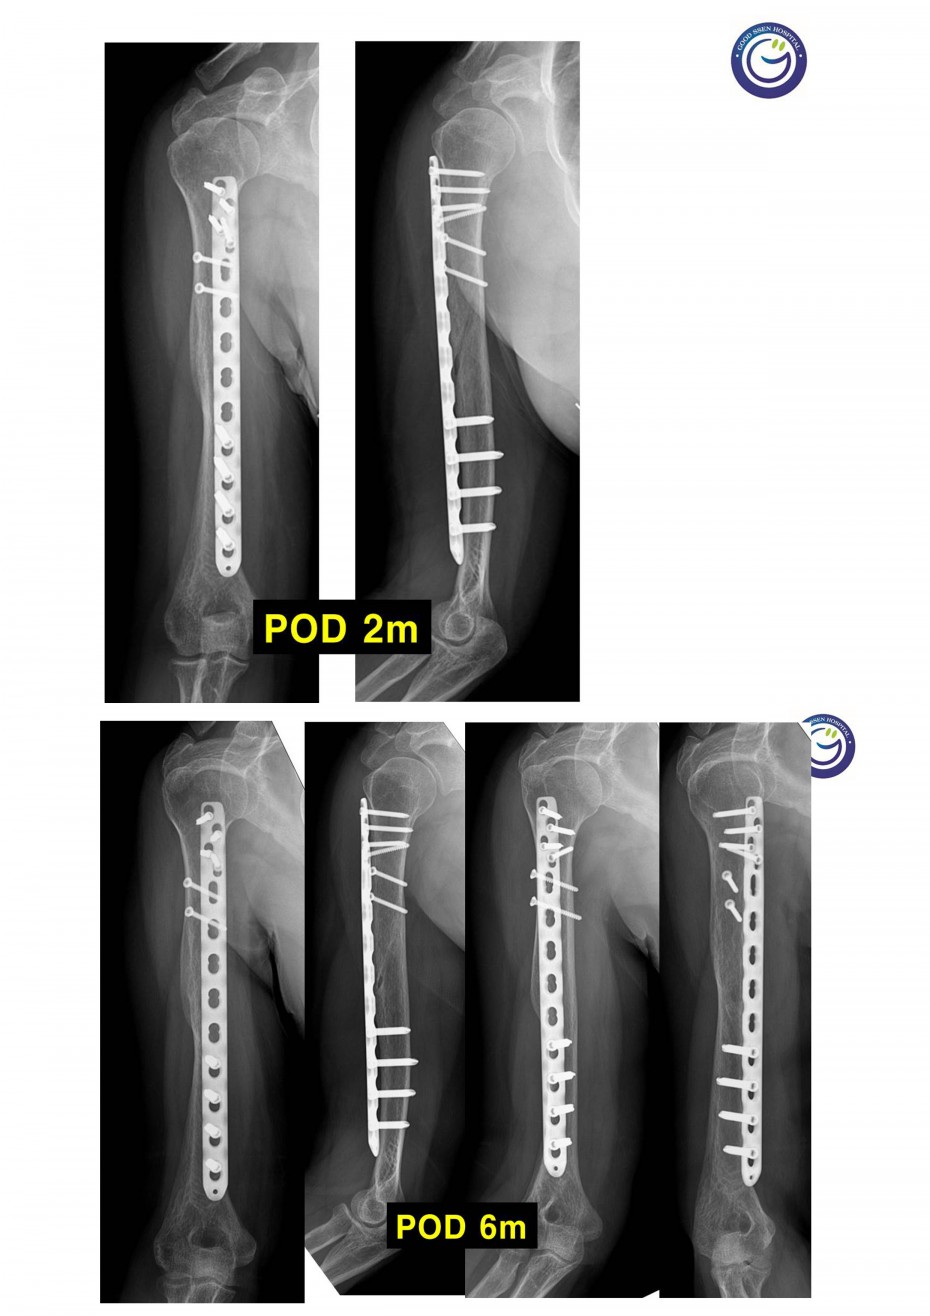

절개없이 고정하는 최소침습적 고정방법 (MIPO)